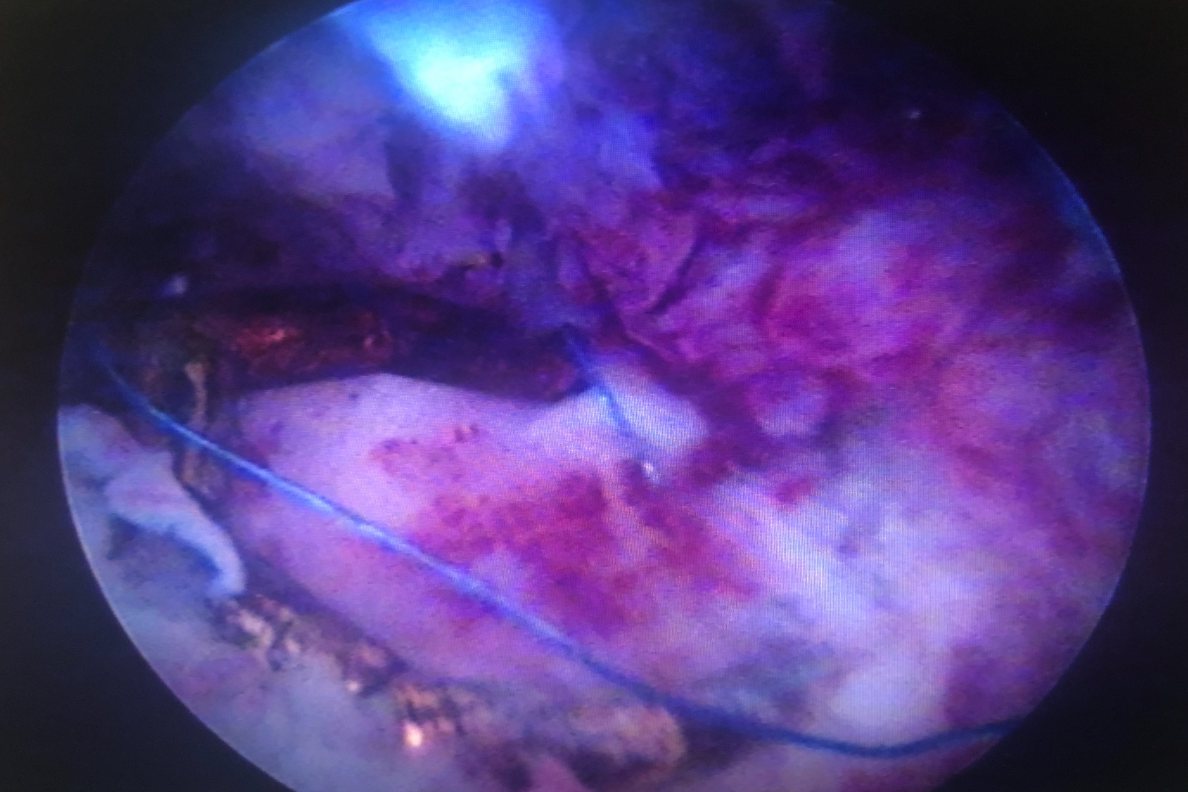

轻度的宫颈粘连可能会出现月经量的减少甚至会出闭经情况,如果宫颈粘连较严重,经血不能够顺畅的排出,积聚在宫腔内,就会在月经期间出现下腹坠胀痛,还可能会影响精子进入到宫腔内造成女性的不孕。